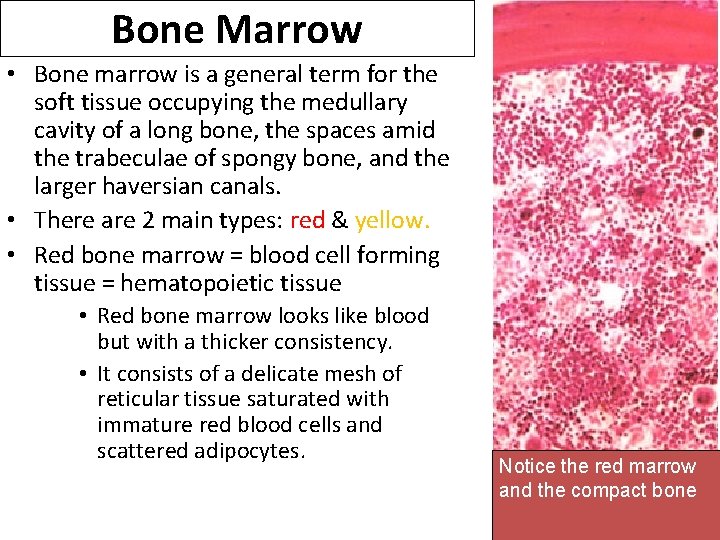

Bone Marrow • Bone marrow is a general term for the soft tissue occupying the medullary cavity of a long bone, the spaces amid the trabeculae of spongy bone, and the larger haversian canals. • There are 2 main types: red & yellow. • Red bone marrow = blood cell forming tissue = hematopoietic tissue • Red bone marrow looks like blood but with a thicker consistency. • It consists of a delicate mesh of reticular tissue saturated with immature red blood cells and scattered adipocytes. Notice the red marrow and the compact bone